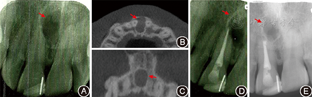

患者男性,33岁,右上前牙跳痛伴鼻底肿痛2年。10年前右上前牙因外伤行修复治疗,后无不适, 2年前出现无明显诱因跳痛伴鼻底处肿痛,可自行缓解。

一般检查示

切1/3可见充填物,叩痛(+),龈唇移行处扪痛(+),轻度肿胀。根尖X线片示

切1/3充填物达牙本质中层,根尖近中侧牙周膜影像中断,可见圆形低密度透射影(1 cm×1 cm)(图3 A)。牙髓活力电测试:

(42)。锥形束CT示鼻底下方直径2 cm低密度透射区,边界清晰,累及

近中根尖区(图3B、图3C)。

术前根尖X线片示根尖近中侧圆形低密度透射影像(箭头);B、C:术前锥形束CT轴位及冠状位,示切牙管处有一球形低密度透射区,致

根尖部唇侧骨壁吸收(箭头);D:

根管治疗后X线片(箭头);E:术后3年根尖X线片示

根尖病灶面积缩小,骨密度升高(箭头)

常规根管治疗(图3D)。1周后手术切除根尖肿物,术中病理结果为鼻腭管囊肿。

术后3年复查,患者无自觉症状,根尖X线片显示

根尖病灶区范围缩小,骨密度逐渐升高(图3E)。